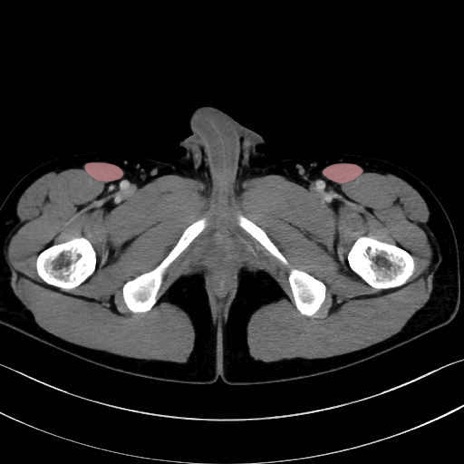

外閉鎖筋 (Obturator externus)

大腿方形筋 (Quadratus femoris)

縫工筋 (Sartorius)